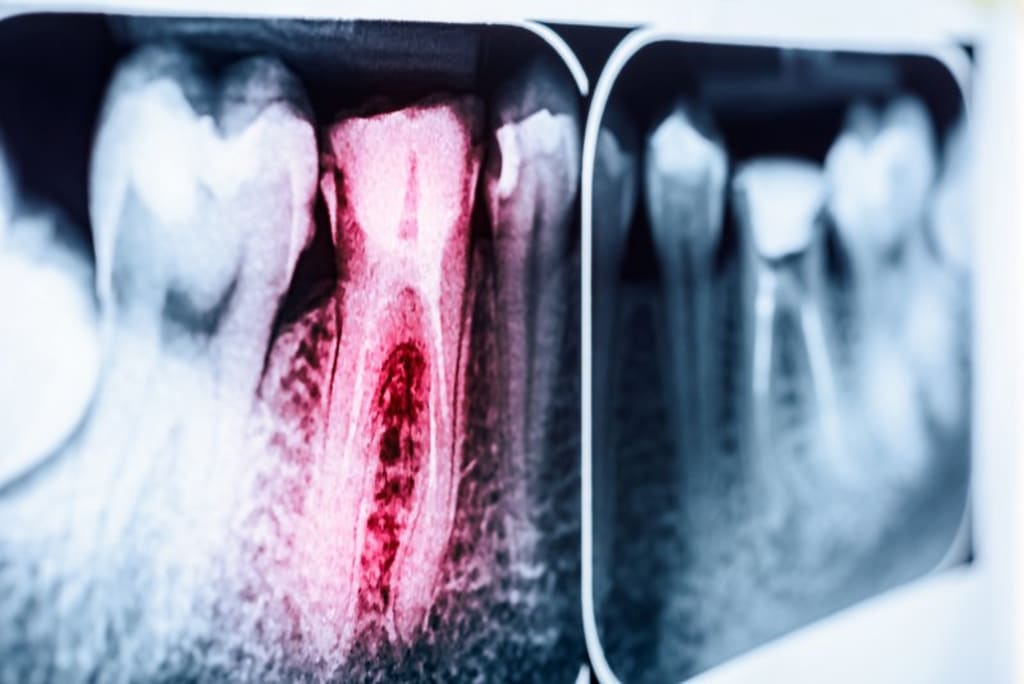

A tooth can become infected if bacteria manage to get past the protective enamel layer (usually as a result of decay or an injury) and attack the inner pulp. This can cause throbbing pain, tooth sensitivity to hot or cold foods, bad breath, and an unpleasant taste in your mouth. However, if the infection starts to spread beyond the tooth, that’s where things can get dangerous.

Once the infection has spread, it can form what’s known as a dental abscess, which is a pocket of pus formed as a result of bacterial infection. Not only are abscesses extremely painful, but they can also lead to sepsis, which is the body’s extreme response to infection. When left unmanaged, sepsis can cause extensive tissue damage, organ failure, and ultimately death.